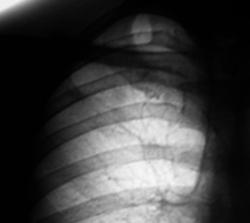

Флюорограмма 2008 г.

4.F-graf..JPG

В 2008 году пациент был взят на контроль и был вызван на дообследование, но "вдруг исчез" из населенного пункта. Но в этом году, а именно сегодня пациента удалось дообследовать.